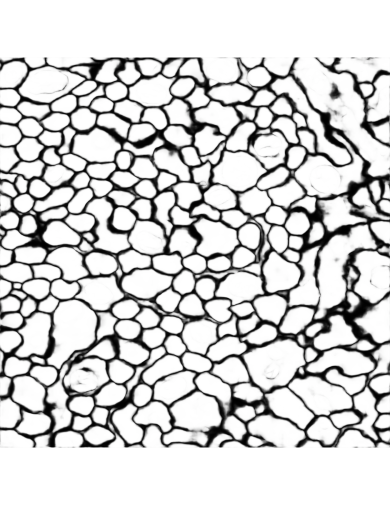

We use the dataset from the open challenge on Circuit Reconstruction from Electron Microscopy Images (CREMI)111https://cremi.org/ to evaluate the proposed invariant CNNs. The CREMI dataset consists of brain electron microscopy images (EM), and the ultimate goal is to reconstruct neurons at the micro-scale level. A critical first step in neuron reconstruction is to segment the EM images. The main objective of neuron segmentation is to distinguish different neuron objects in the electron microscopy images. A common way for segmenting EM images is to predict the neuronal boundaries in the images [15]. For each pixel in the dense prediction output, there will be two labels with corresponding probabilities. Class 1 pixels correspond to boundaries in the image, and class 0 pixels correspond to all other structures. This task has an additional problem of imbalanced samples since there are far less boundary pixels in the image than non-boundary pixels. Thus, the commonly-used accuracy metric may not correctly reflect the performance of dense prediction models. In this situation, the ROC curve is used to evaluate models involved in this work, which could avoid the influence of imbalanced labels.

Refer to captionRefer to captionRefer to captionRefer to captionInput imageBaseline without data augmentationBaseline with data augmentationNew model without data augmentationRefer to captionRefer to captionRefer to captionRefer to captionInput imageBaseline without data augmentationBaseline with data augmentationNew model without data augmentation\begin{array}[]{cccc}\includegraphics[width=203.80193pt]{FIG/outputsub1.pdf}&\includegraphics[width=203.80193pt]{FIG/outputsub2.pdf}&\includegraphics[width=203.80193pt]{FIG/outputsub3.pdf}&\includegraphics[width=203.80193pt]{FIG/outputsub4.pdf}\\ \mbox{Input image}&\mbox{Baseline without data augmentation}&\mbox{Baseline with data augmentation}&\mbox{New model without data augmentation}\end{array}

Figure 8: Comparison of the results generated by the three models. The inputs are brain electron microscopy images, and the outputs are boundaries of neurons.

IV-E Analysis of Results

The dense prediction outputs of three models are given in Figure 8. Figure 7 shows the training loss of the three models at different iterations. The training loss of the baseline model without data augmentation is the highest among the three models. The new model without data augmentation even has the lowest training loss along the whole training iterations. This means the property of rotation and flip invariance in the new model help improve the training, since it could deal with features with arbitrary rotation and flip transformations. The baseline model without data augmentation does not have this invariance capability. The baseline model with data augmentation may be trained to learn this property but with much more iterations. From these results, it is clear that the baseline model with data augmentation has larger loss than the new model until after 35,000 iterations. But the loss of the baseline model without data augmentation is always higher than that of the new model. The gap between the loss curves of the baseline model without data augmentation and the new model even increases as iteration number increases.

Table I shows the model evaluation results using AUC values. Since the prediction output labels are imbalance, AUC values would be more meaningful in the evaluation. The AUC values of the new model and baseline model with data augmentation are similar and higher than that of the baseline model without data augmentation. This shows that the new model has very similar performance compared to the baseline model with data augmentation. This also demonstrates that data augmentation usually leads to improved performance, a results that is consistent with prior observations [16]. Figure 6 gives the ROC curves of three models.